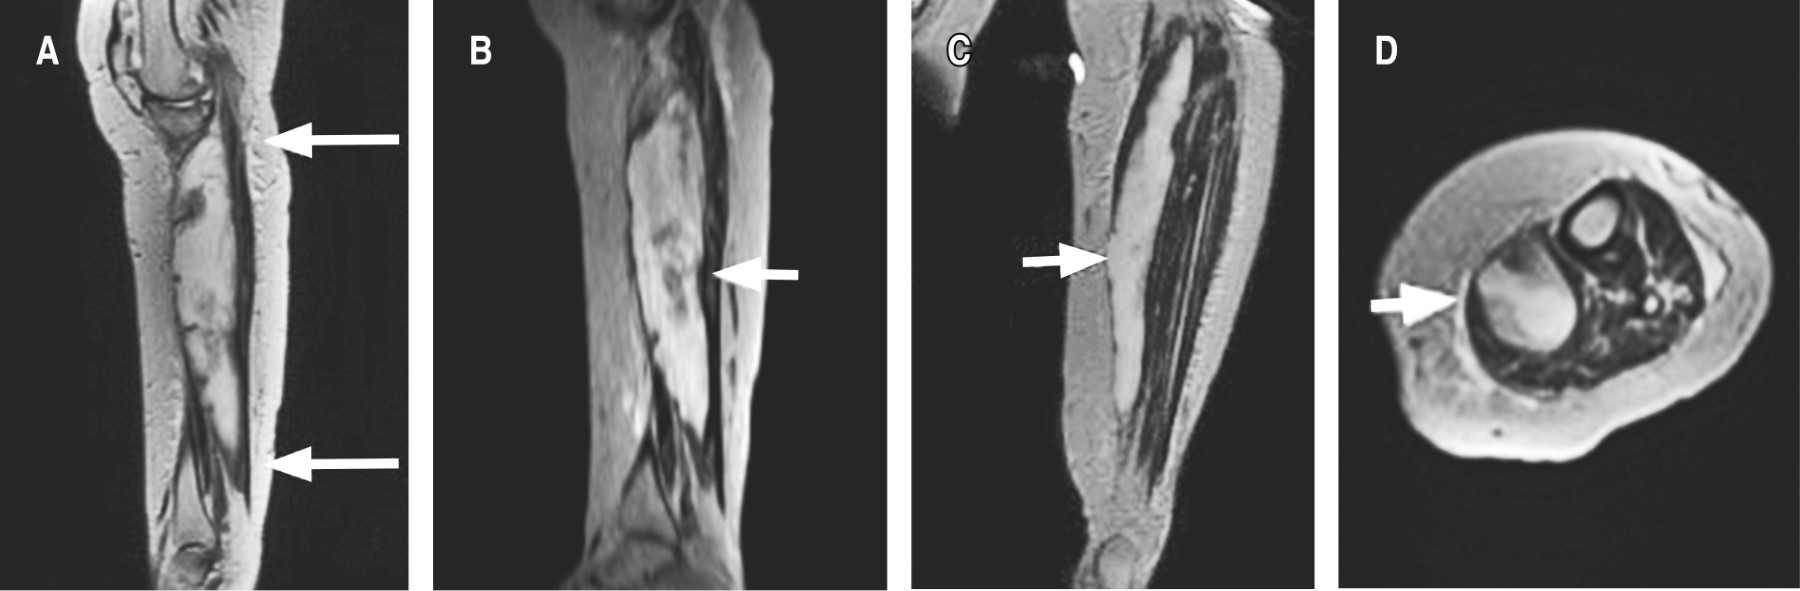

Se continuó abordaje diagnóstico con resonancia magnética de rodilla izquierda en la que se reportó: quiste de Baker, desgarro del ligamento cruzado anterior, derrame articular, contusión y acodamiento del ligamento cruzado posterior, desgarros meniscales complejos (Figura 3). En las imágenes obtenidas se visualizó un quiste de Baker de gran tamaño que no podía ser correctamente definido por las grandes dimensiones del mismo, así como por falta de cortes distales para observar bien el tamaño. Por tal motivo, se solicitó complemento de resonancia magnética de pierna izquierda simple y contrastada con proyecciones angiográficas: trayectos vasculares regulares en todos los segmentos explorados. Se observa desplazamiento de estructuras vasculares que no compromete el calibre ni morfología (Figura 4). Dicho desplazamiento se debe al efecto de masa que condiciona una lesión quística que corresponde a quiste de Baker que se extiende hasta tercio distal de la pierna, el cual presenta heterogeneidad intraluminal, con pliegues parciales de la sinovial que es de grosor uniforme y delgada, reportándose con medidas de 31 × 4.6 × 3.9 cm, con volumen de 289 cm3; posterior a la aplicación del gadolinio, no muestra reforzamiento que sugiera otra patología. Edema en tejido graso subcutáneo, identificando colecciones pequeñas adyacentes a fascias musculares de caras medial y lateral en tercios medio y proximal (Figura 5). Como complemento, se realizaron pruebas de laboratorio para descartar artritis reumatoide; se encuentra factor reumatoide y anticuerpos contra péptido cíclico citrulinado negativos; además, la paciente no cumplía con el resto de los criterios diagnósticos para artritis reumatoide. El tratamiento inicial para la paciente fue manejo conservador con antiinflamatorios no esteroideos e inicio de fisioterapia. Se propuso manejo quirúrgico, así como punción y drenaje del quiste, pero, al contar con los antecedentes cardiovasculares ya mencionados, la paciente rechazó este manejo y se continuó con un tratamiento conservador a base de antiinflamatorios, fisioterapia y vigilancia. A los seis meses de seguimiento, la paciente presenta mejoría clínica y funcional basada en la exploración física y en la sintomatología. Se solicitan estudios de imagen de control, los cuales rechaza la paciente por motivos personales; se decide continuar con seguimiento en la consulta externa con base en clínica y funcionalidad.